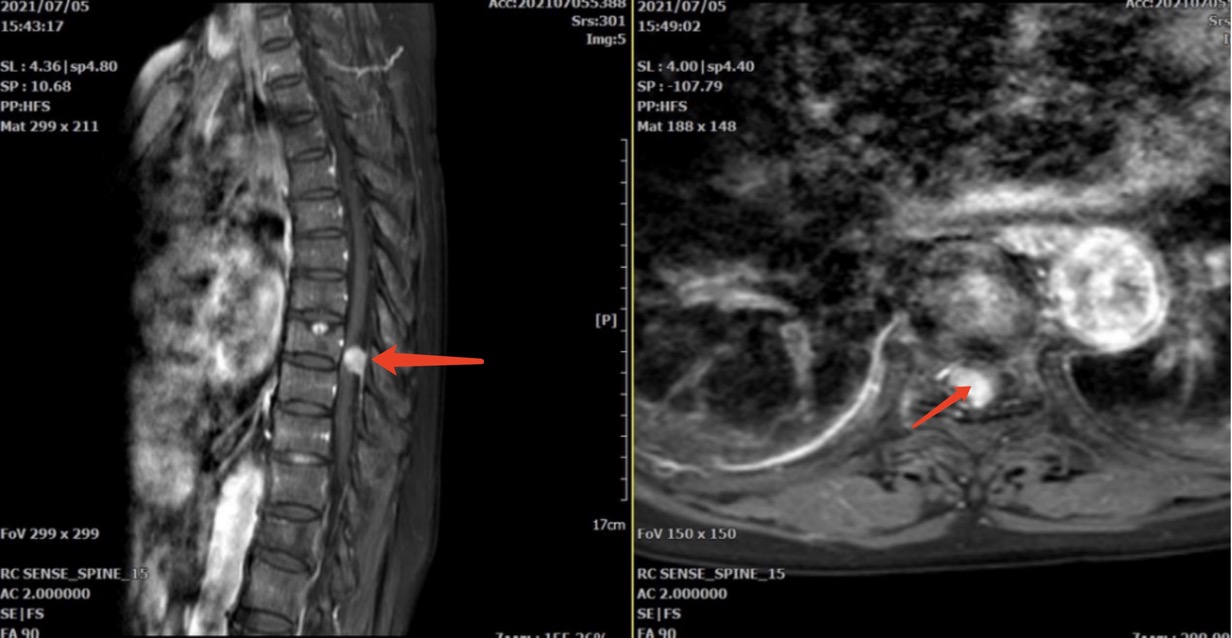

骨伤科副主任王庆敏详细诊查后,考虑叶阿婆的症状为胸8/9椎管水平的脊膜瘤压迫脊髓神经引起。增强磁共振清楚显示椎管内占位面积已经超过80%,手术指征明确。由于胸椎管狭窄、手术操作空间小,损伤脊髓神经的风险极高,如术中止血不彻底,术后血肿压迫也会导致患者瘫痪。